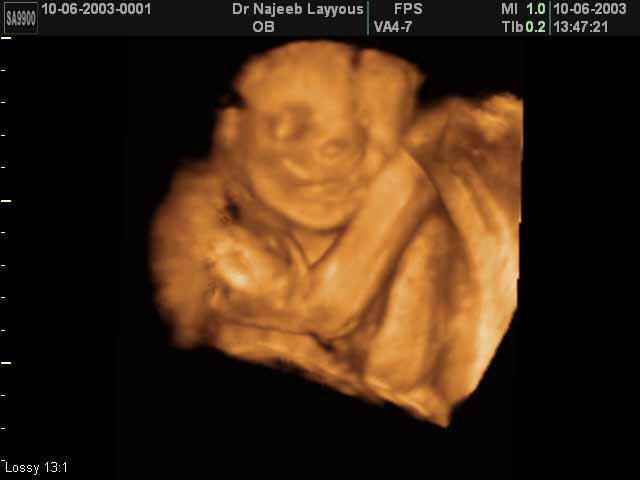

3D second trimestre échographie Photos de numérisation - deuxième partie de la grossesse | Dr N Layyous

3D second trimestre échographie Photos de numérisation - deuxième partie de la grossesse